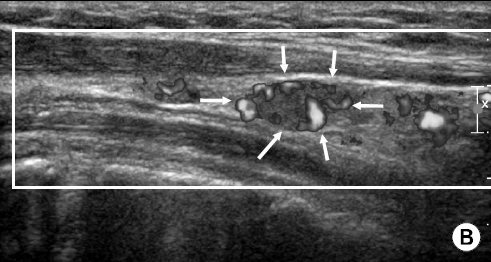

위 초음파 사진은 임파선 주위에 혈류 도플러 검사를 한 모습인데 임파선 주위로 혈관들이 비정상적으로 많이 발달해 있습니다.